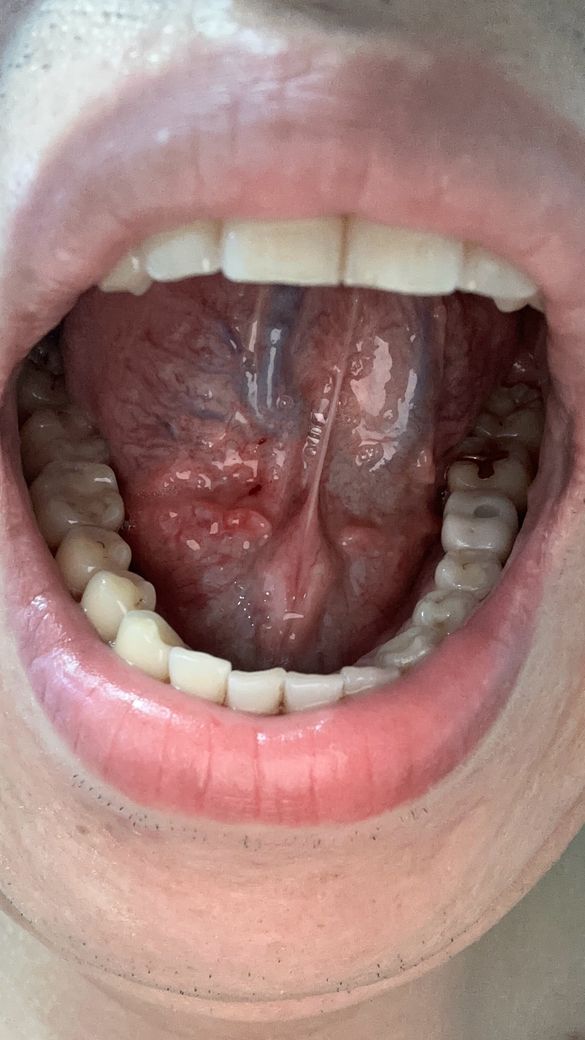

양치하다가 칫솔로 눌렀는데 피나는거처럼 됬어요

빨갛게 된부분이 있는것같고 그래서 이거 병원가봐야되는지 그냥 냅둬도 괜찮음지 궁금해요 어떻게하는게 좋을까요?? 병원은 무슨과인가요?

• 1번 째 사진

양치 중 칫솔로 인해 잇몸이 붉어지고 피가 나는 것은 잇몸 염증의 초기 증상일 수 있습니다. 칫솔질 시 잇몸에 과도한 힘이 가해지거나, 치석이나 치태가 쌓여 잇몸이 자극받았을 가능성이 있습니다. 우선 2~3일 정도는 부드러운 칫솔모를 사용하여 잇몸에 자극을 최소화하고, 치실이나 치간칫솔을 사용하여 꼼꼼하게 치아 사이를 청결하게 관리해주세요.

만약 며칠 후에도 증상이 호전되지 않거나, 붓기나 통증이 심해진다면 치과에 방문하여 정확한 진단을 받아보는 것이 좋습니다. 치과에서는 잇몸 상태를 확인하고 필요한 경우 스케일링이나 다른 치료를 통해 잇몸 건강을 회복할 수 있습니다.